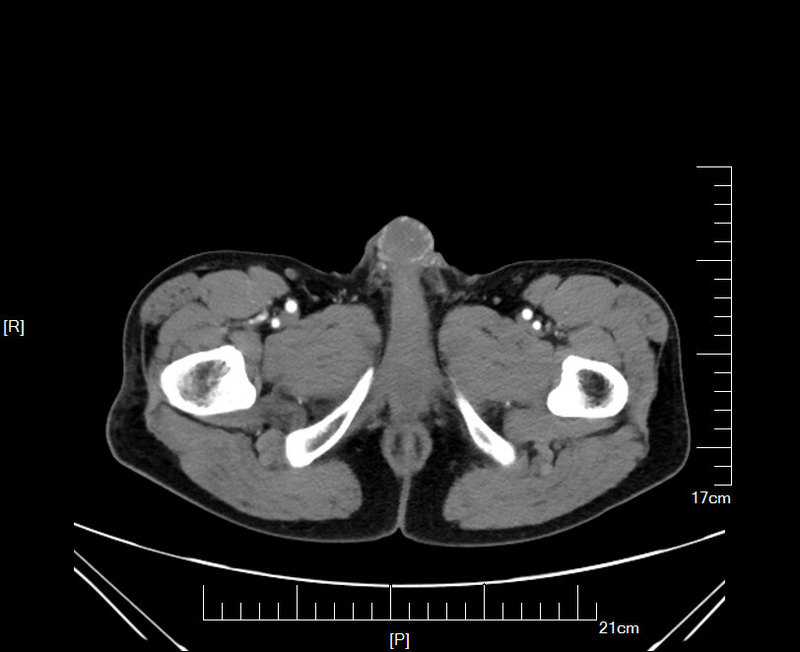

1例陰莖癌(70歲)術(shù)后輔助放療田某某(ZW),男,70歲carcinomaofpenispenilecancer陰莖的淋巴引流主要有3條途徑:1.包皮和陰莖干體皮膚及皮下組織的淋巴引流到位于闊筋膜上方的淺表腹股溝淋巴結(jié)2.陰莖頭及海綿體的淋巴流向恥骨聯(lián)合前的淋巴叢,由此通向兩側(cè)入腹股溝深淺淋巴結(jié)或骼外淋巴結(jié),舟狀窩和陰莖部尿道的淋巴隨著陰莖的淋巴一起引流到腹股溝深淺淋巴結(jié)。3.尿道球膜部和前列腺部的淋巴:(1)部分經(jīng)恥骨聯(lián)合下方進(jìn)入骼外淋巴結(jié)。(2)部分進(jìn)入閉孔肌和骼內(nèi)淋巴結(jié)。(3)部分進(jìn)入前淋巴結(jié)。陰莖兩側(cè)的淋巴引流之間有著豐富的交通網(wǎng),從臨床實(shí)踐來看陰莖的淋巴引流可以認(rèn)為是雙側(cè)的。位于腹壁靜脈和大隱靜脈結(jié)合部位的上方或中間的前哨淋巴結(jié),是陰莖癌最早的淋巴引流部位,這組淋巴結(jié)對(duì)判斷腫瘤的范圍非常重要,如果這組淋巴結(jié)未受侵,就沒有必要進(jìn)行腹股溝淋巴結(jié)清掃。在腹股溝淋巴結(jié)未受侵的情況下,盆腔淋巴結(jié)很少受侵。陰莖癌治療方法主要有手術(shù),放射治療,激光治療和化療。治療方法的選擇取決于原發(fā)腫瘤侵犯范圍和淋巴結(jié)轉(zhuǎn)移情況。原發(fā)腫瘤的處理主要和腫瘤大小,侵犯深度,腫瘤分級(jí)有關(guān)。對(duì)于腫瘤較小,分期早和高分化的原發(fā)腫瘤可采取保留陰莖治療,如器官保留性手術(shù)、放射治療或激光治療。病變較晚的腫瘤需采用陰莖部分或陰莖全部切除。陰莖癌腹股溝淋巴結(jié)轉(zhuǎn)移率很高,pT2-4.和分化差的陰莖癌,腹股溝亞臨床轉(zhuǎn)移達(dá)66%~83%,腹股溝淋巴結(jié)清掃及放療可明顯改善生存率。陰莖癌的生存率和淋巴結(jié)轉(zhuǎn)移狀況有關(guān),淋巴結(jié)陰性病人的總生存率可達(dá)85%~90%。腹股溝淋巴結(jié)轉(zhuǎn)移時(shí),5年生存率降至50%以下,特別是同時(shí)出現(xiàn)多發(fā)淋巴結(jié)轉(zhuǎn)移,雙側(cè)淋巴結(jié)轉(zhuǎn)移或轉(zhuǎn)移淋巴結(jié)固定時(shí),預(yù)后更差。在有組織病理證實(shí)的腹股溝淋巴結(jié)轉(zhuǎn)移時(shí),許多作者建議同時(shí)做盆腔淋巴結(jié)清掃,這部分病人的生存率僅為9%~20%,大部分死于遠(yuǎn)處轉(zhuǎn)移。手術(shù)治療陰莖癌手術(shù)治療方式取決于病變范圍和程度,包括包皮環(huán)切、局部切除、陰莖部分切除和根治性陰莖切除。理想的手術(shù)應(yīng)該是切除病變的同時(shí)保留排尿和性功能,但有時(shí)由于病變廣泛很難做到這一點(diǎn)。根治性手術(shù)尤其是陰莖全切術(shù),會(huì)對(duì)患者的心理造成極大的損傷。局限在包皮的病灶可采用廣泛的包皮環(huán)切術(shù);包皮環(huán)切術(shù)的局部復(fù)發(fā)率為40%。龜頭部的病灶通常可采用陰莖部分切除術(shù);如果能夠取得2cm的手術(shù)邊緣區(qū),就應(yīng)選擇陰莖部分切除術(shù),有些患者在經(jīng)過陰莖部分切除手術(shù)后仍有可能保持性交的能力。Jensen等人曾報(bào)道45%保留4~6cm陰莖殘端和25%保留2~4cm陰莖殘端的患者(一)原發(fā)灶處理陰莖癌部分切除術(shù)大部分復(fù)發(fā)在術(shù)后12~18個(gè)月。局部復(fù)發(fā)應(yīng)考慮進(jìn)一步手術(shù)挽救治療。尿道仍可以有性生活。復(fù)發(fā)時(shí)生長(zhǎng)迅速,易侵犯陰莖海綿體,手術(shù)應(yīng)考慮切除整個(gè)尿道和可能受侵的區(qū)域。(二)區(qū)域淋巴結(jié)處理1.分化好、腫瘤局限于龜頭或T、腹股溝淋巴結(jié)陰性(T./T,NM)。腹股溝淋巴結(jié)檢查未發(fā)現(xiàn)可疑病變。建議臨床密切觀察,每2月做一次檢查,持續(xù)2~3年。1993年印度報(bào)道一組大的治療結(jié)果表明,預(yù)防性淋巴結(jié)清掃、活檢或觀察組的5年生存率相同。2.分化差、病變較廣泛,但腹股溝淋巴結(jié)臨床陰性時(shí)(T,N)。臨床檢查腹股溝淋巴結(jié)陰性則要對(duì)于前哨淋巴結(jié)進(jìn)行B超引導(dǎo)下的細(xì)針穿刺和淋巴結(jié)活檢,如果沒有轉(zhuǎn)移,建議臨床密切觀察每2月做一次檢查,持續(xù)2~3年。如果有轉(zhuǎn)移,就需要行腹股溝淋巴結(jié)清掃,清掃結(jié)果如果只有-個(gè)淋巴結(jié)轉(zhuǎn)移,建議臨床密切觀察,每2月做一次檢查,持續(xù)2~3年。如果兩個(gè)或以上淋巴結(jié)轉(zhuǎn)移建議做輔助放療(同側(cè))。3.腹股溝淋巴結(jié)陽性的病人,建議行淋巴結(jié)清掃,兩個(gè)或以上的淋巴結(jié)轉(zhuǎn)移時(shí),建議行輔助性放療(同側(cè)),或必要時(shí)做化療。4.如果盆腔淋巴結(jié)腫大時(shí),需要同時(shí)行盆腔和腹股溝淋巴結(jié)切除,并行盆腔和腹股溝淋巴結(jié)放療。文獻(xiàn)報(bào)道淋巴結(jié)清掃的5年生存率為20%~50%;中國(guó)醫(yī)學(xué)科學(xué)院腫瘤醫(yī)院壽建忠報(bào)道53例陰莖癌腹股溝淋巴結(jié)轉(zhuǎn)移的病人,其中22例為陰莖手術(shù)時(shí)發(fā)現(xiàn),31例為術(shù)后隨訪中發(fā)現(xiàn),采用腹股溝淋巴結(jié)切除聯(lián)合術(shù)后放療者40例,1、2、5年生存率分別為60%、47.5%和37.5%,副作用少見:說明腹股溝轉(zhuǎn)移淋巴結(jié)切除聯(lián)合放療是一種有效的治療手段,生存率與腹股溝淋巴結(jié)清掃術(shù)的結(jié)果相似,但減少了清掃術(shù)的并發(fā)癥。三、放射治療陰莖癌的放射治療是保存器官和功能的重要治療手段,這一點(diǎn)對(duì)于僅于龜頭部有很小病變的精充沛年輕的男性患者尤為重要,早期陰莖癌放射治療可以根治,對(duì)經(jīng)選擇的病人90%以上經(jīng)放射治療可保留性功能;:一般55%~86%的病人可以保留器官,局部控制率在60%~90%可保留性功能。部分陰莖切險(xiǎn)或全切后,引起明顯的心理和生理障礙。對(duì)晚期陰莖癌放療可起姑息性或減輕癥狀的作用。BackgroundSquamouscellcarcinomaofthepenisisrare;treatmentneedstoconsiderboththeprimarylesionandthepotentialforlymphaticdissemination.Bilaterallymphnodeinvolvementiscommonduetotherichpenilelymphaticdrainage.Lymphnodespreadgenerallyoccursinapredictablemanner,involvingsuperficialinguinal,thendeepinguinalandthenpelviclymphnodes.Approximately20-30%ofpatientswithpositiveinguinalnodeshavepositivepelvicnodes.Lymphnodestatusisamajorprognosticfactorforpenilecancer.Surgeryisthemainstayoflocoregionaltreatment.Thereisalackofhighlevelevidencetoguidemanagement.